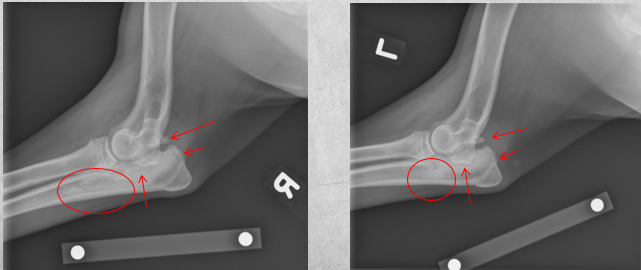

Q

8 months old female German Shepherd

Painful elbows

A

Both elbows: the anconeal process is ununited, the margins of the anconeal process and olecranon are markedly irregular and periosteal proliferation is present.

Marked intramedullary sclerosis of the olecranon and subtrochlear region of the proximal ulna is visible.

Diagnosis: Ununited anconeal process (UAP) and panosteitis of the ulnas.